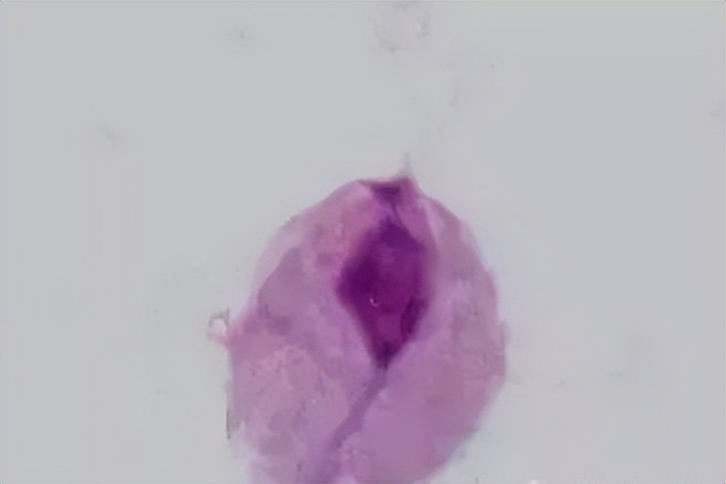

阴道清洁度是利用显微镜对阴道分泌物湿片和染色涂片检查,观察其清洁度和有无特殊细菌及细胞等,确认阴道清洁度,判断阴道有无炎症,还可以进一步诊断炎症的原因。

阴道清洁 Ⅰ 度:镜下以阴道杆菌为主,并可见大量上皮细胞。

阴道清洁 Ⅱ 度:有部分阴道杆菌及上皮细胞,部分白细胞和杂菌。

阴道清洁 Ⅲ 度:少量阴道杆菌和上皮细胞,大量白细胞和其他杂菌。提示炎症,如阴道炎宫颈炎。

阴道清洁 Ⅳ 度:镜下无阴道杆菌,几乎全是白细胞和大量杂菌。多见于严重阴道炎,如淋球菌阴道炎、滴虫性阴道炎等。

白细胞

在悬滴液中,正常白带高倍视野仅能看到一、二个白细胞,如存在大量白细胞应考虑滴虫病或宫颈炎;念珠菌病及细菌性阴道病白带的悬滴液涂片中白细胞少。